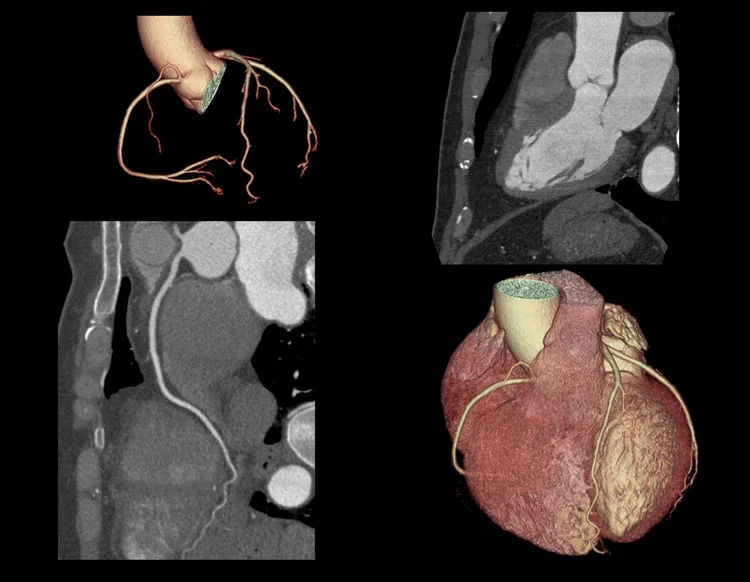

As the name suggests, this is a CT scan of your heart, or more specifically the coronary arteries. Coronary arteries are blood vessels that bring blood to the muscles of the heart. If a coronary artery is narrowed or blocked, a person can experience angina chest pain or in more severe circumstances, a heart attack.

A cardiac CT is used specifically to examine the coronary arteries. It also shows the rest of the heart but MRI is better at assessing other structures.